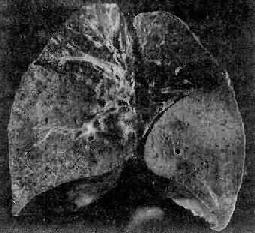

图9-16 大叶性肺炎

左下叶实变,呈灰白色,肺叶明显肿胀